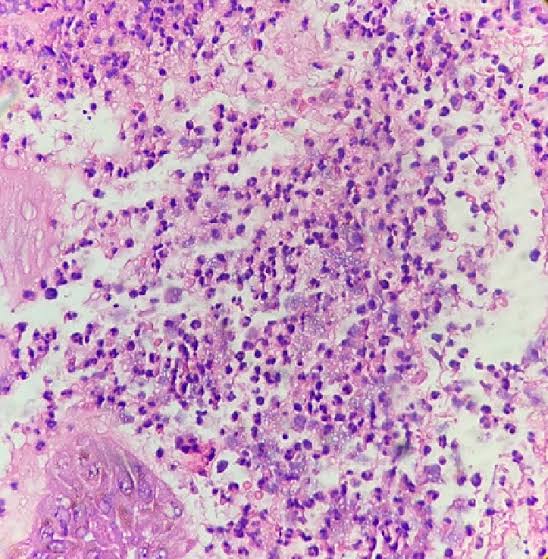

Abscesso com Infiltrado Inflamatório Agudo

A imagem mostra um infiltrado inflamatório denso composto por neutrófilos, característico de um abscesso ou uma inflamação aguda severa. Os neutrófilos são as primeiras células imunes a serem recrutadas para o local de uma infecção bacteriana ou lesão tecidual. Eles fagocitam patógenos e detritos celulares e liberam enzimas e mediadores inflamatórios. Essa resposta imune inata é crucial para combater infecções, mas a liberação excessiva de mediadores pode também contribuir para o dano tecidual.